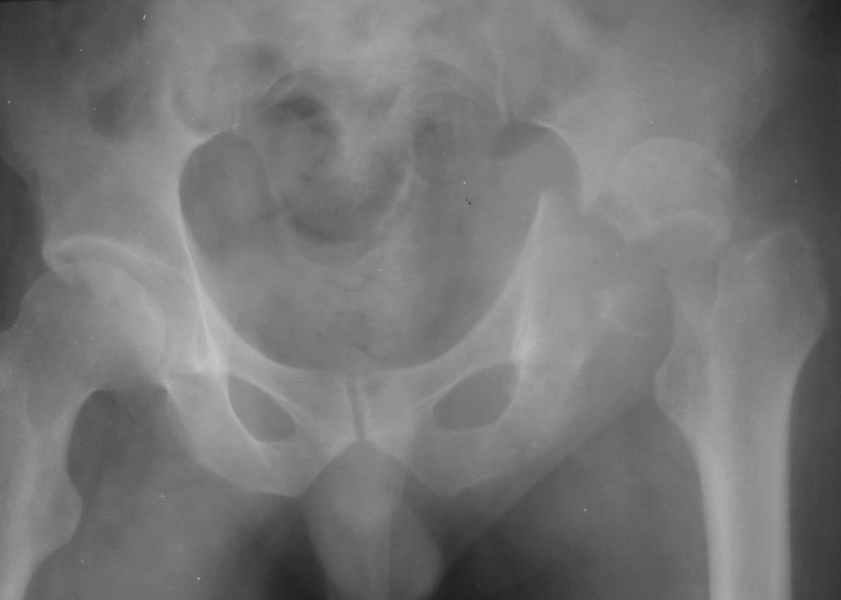

Дорогие коллеги, Поступил пациент, 5 месяцев, как сломался.

Поступил для эндопротезирования, но наши корифеи засомневались, не собрать ли сначала таз. Есть ли смысл собирать аппаратом закрыто?